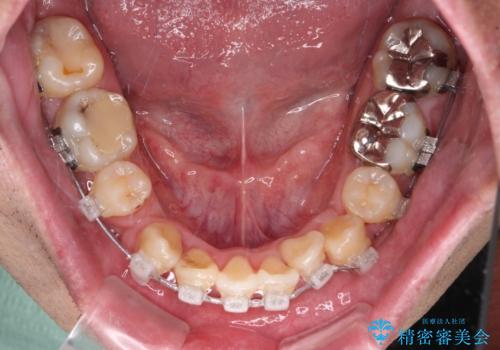

- 矯正装置

- クリアブラケット

- 上下の八重歯やデコボコを気にして来院された患者様です。

上下ともに八重歯が顕著であったので、上下左右第一小臼歯4本を抜歯し、ワイヤー装置にて矯正治療を行うこととしました。

デコボコが強いことが原因で歯間部に汚れが溜まりやすい状態でしたが、矯正前にできる限り汚れが少なくなるようにブラッシングなどの指導を行い、口腔状態が改善された後にワイヤー装置を装着することとしました。

結婚式をきっかけに矯正治療を決意したとのことでしたが、挙式までの期間があまりにも短かったために、結婚式後に治療を開始することとなりました。

1年以上のゆとりを持って矯正治療を始める必要があります。